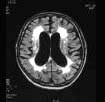

问题 患者,50岁,高血压病史,反复出现TIA、腔隙性梗死,痴呆,MRI如图,下列哪项诊断可能最大 ( )

选项 A、Alzheimer病 B、CJD C、路易体痴呆 D、Pick病 E、血管性痴呆

答案 E